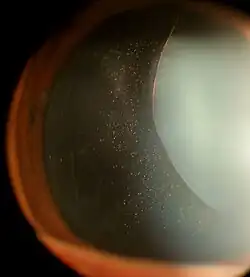

Zonules of Zinn visible in a case of an exceptionally dilated pupil with lens subluxation in Marfan syndrome

The zonules of Zinn are difficult to visualize using a slit lamp, but may be seen with exceptional dilation of the pupil, or if a coloboma of the iris or a subluxation of the lens is present.[8] The number of zonules present in a person appears to decrease with age.[5] The zonules insert around the outer margin of the lens (equator), both anteriorly and posteriorly.[9]